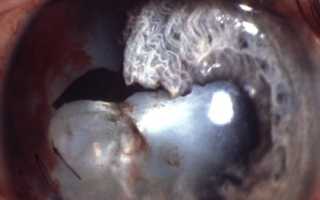

Первые изменения хрусталика при ксеногенном халькозе выражаются в накоплении соединений меди в эпителии хрусталика в форме диска с радиально отходящими от него лучами (лепестками). Это образование имеет зеленовато-желтую окраску и напоминает изображение подсолнечника.

Из-за той характерной картины катаракта при халькозе получила название катаракты подсолнечника. Обычно она бывает видна при боковом освещении и при биомикроскопии, а в проходящем свете длительное время остается незаметной. Хрусталик полностью мутнеет через несколько месяцев или лет.